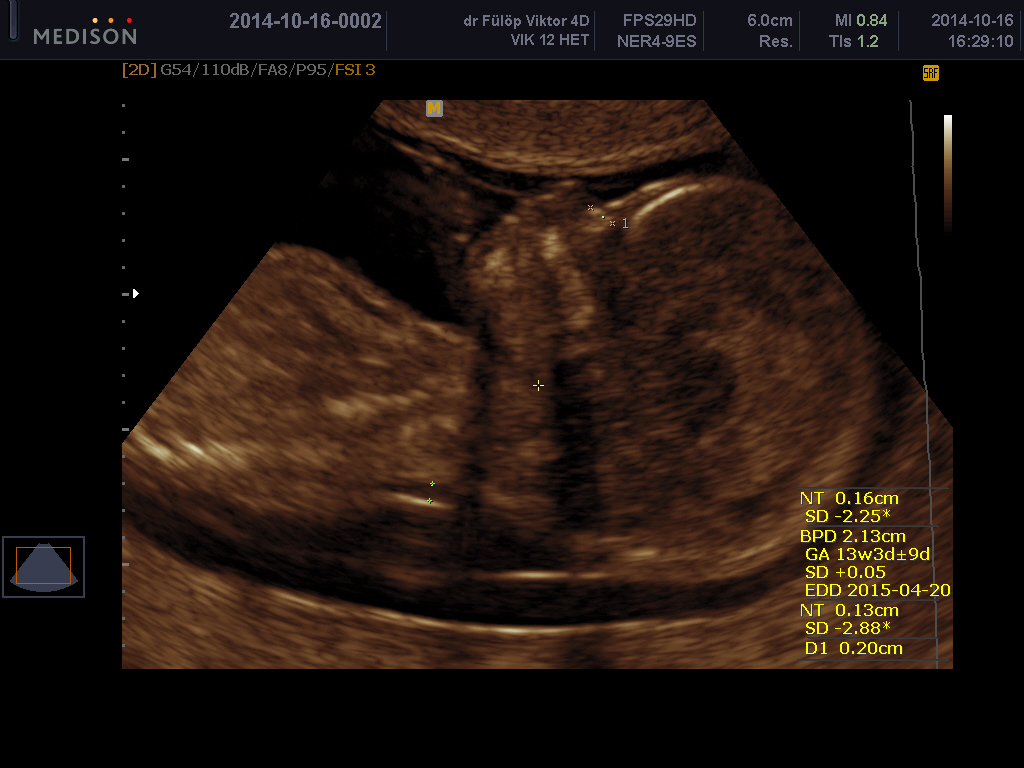

FMF-standard – Az első trimeszteri fejlődési rendellenesség szűréshez fontos a megfelelő technikával, megfelelő síkban mért nyaki redő (NT).

NT: a tarkóredő vastagsága